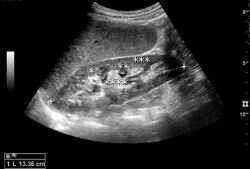

Cortical thickness should be estimated from the base of the pyramid and is generally 7–10 mm. If the pyramids are difficult to differentiate, the parenchymal thickness can be measured instead and should be 15–20 mm (Figure 3). The echogenicity of the cortex decreases with age and is less echogenic than or equal to the liver and spleen at the same depth in individuals older than six months. In neonates and children up to six months of age, the cortex is more echogenic than the liver and spleen when compared at the same depth.[1]

Figure 3. Measures of the kidney. L = length. P = parenchymal thickness. C = cortical thickness.[1]